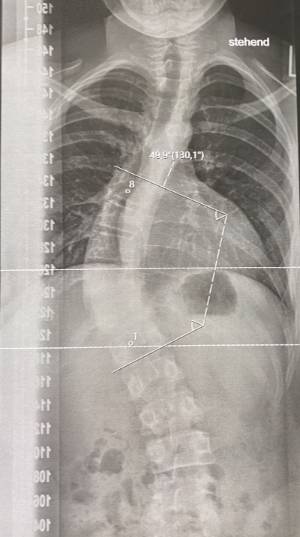

X-ray image of an adolescent idiopathic scoliosis with 50º Cobb angle.